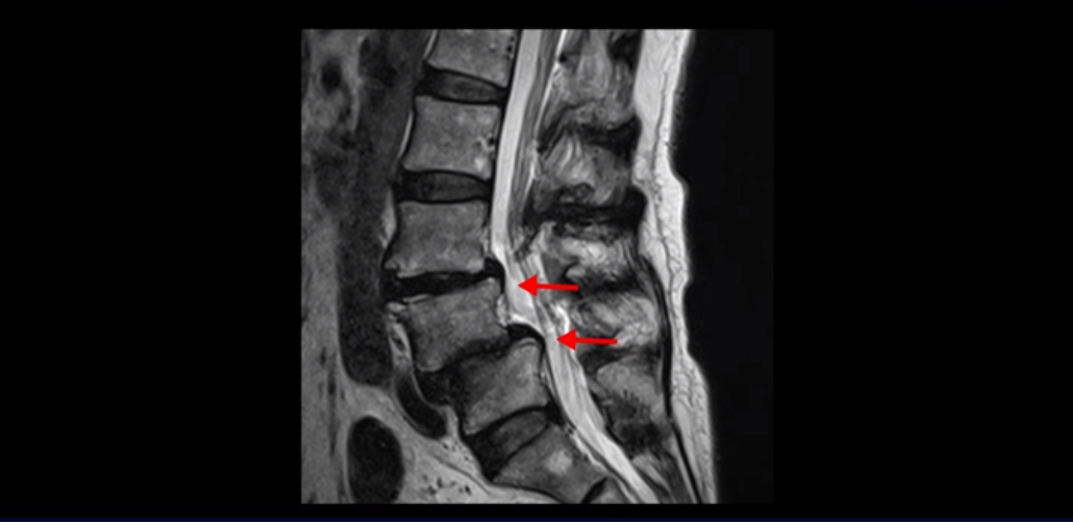

제가 이분 MRI 보면서 설명 드린 후 어떻게 대학병원에서 나사 6개 박는 수술밖에 방법이 없다고 들은 전방전위와 협착증 환자가 비수술 근육재활치료로 좋아질 수 있는지, 치료는 어떻게 하는 건지 자세히 설명 드리도록 하겠습니다.

MRI를 보면 보시다시피 전방전위가 2마디가 있는데, 4번 5번 마디는 2단계로 매우 심합니다.

이렇게 전방전위가 있으면 신경 구멍을 좁히게 되니까 협착이 다른 사람에 비해 더 쉽게 올 수 있습니다. 그래서 오른쪽 신경 구멍을 보면 3번 4번, 4번 5번 추간공이 많이 좁아져 있습니다.

왼쪽 신경 구멍도 두 마디가 좁아져 있어서

이분은 오른쪽, 왼쪽 양쪽 엉덩이와 다리가 다 저리고 아파 못 걷습니다. 이렇게 전방전위와 협착도 심하니까 국내 최상급 대학병원에서도 나사 6개 박는 유합술을 반드시 해야 한다는데, 어떻게 이런 상태가 수술 없이 치료가 가능할까요? 지금부터 설명 드립니다.